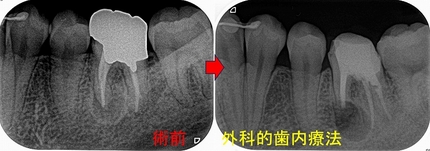

根管充填+レジンコア+レジン充填まで

2026 EEdental YOA (5).jpg

術前⇒術中⇒術後

2026 EEdental YOA (7).jpg

術前の遠心ラインだと、オーバーカウントゥアーとレスカウントゥアーが存在していたのでその辺りも修正